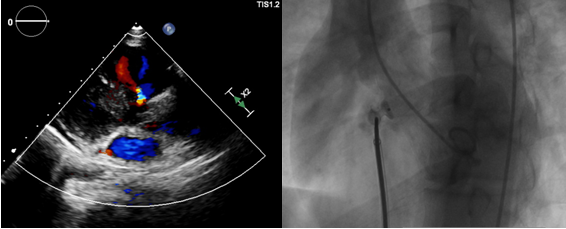

此次手术由周亚峰副院长指导,陈弹主任医师主刀,董瑞庆博士一助,术中杨俊华主任医师全程超声配合。考虑患儿年龄尚轻,室间隔缺损面积较小,心血管内科在术前充分准备手术方案。此次手术的难点在于:建立动静脉轨道困难,DSA下如此小的室缺插管,好比是“穿绣花针”。陈主任通过几次尝试,最终“柳暗花明”,成功建立动静脉轨道,置入了6mm大小的“迷你版”封堵器,术中超声心动图及DSA造影确认封堵完全,心电监护亦未见房室传导阻滞,手术顺利完成。术后第二天下午,小李已正常下床活动,恢复日常生活工作。